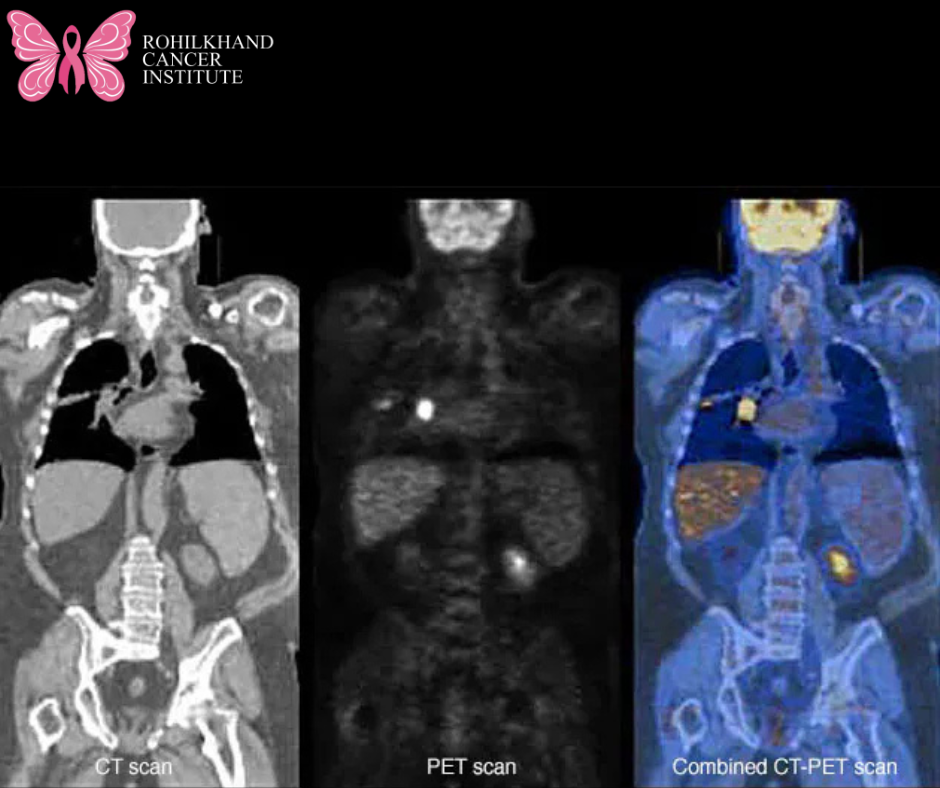

A positron emission tomography (PET) scan is an imaging test that can help reveal the metabolic or biochemical function of your tissues and organs. The PET scan uses a radioactive drug called a tracer to show both typical and atypical metabolic activity. A PET scan can often detect the atypical metabolism of the tracer in diseases before the disease shows up on other imaging tests, such as computerized tomography (CT) and magnetic resonance imaging (MRI).

The tracer is most often injected into a vein within your hand or arm. The tracer will then collect into areas of your body that have higher levels of metabolic or biochemical activity. This often pinpoints the location of the disease. The PET images are typically combined with CT or MRI and are called PET-CT or PET-MRI scans.

The radiologist may compare your PET images with images from other tests you’ve undergone recently, such as an MRI or CT. Or the PET images may be combined to provide more detail about your condition.